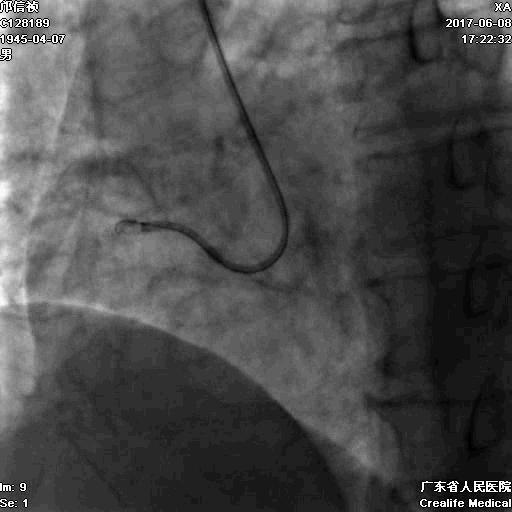

1.正向2.5*15mm球囊扩张,Reverse CART

2.Guidezilla延长导管辅助下,逆向导丝进入正向GC

1.更换RG3导丝

2.GC送入普通导丝,保护LM

RCA闭塞段球囊扩张后IVUS

支架术后造影结果

支架术后IVUS